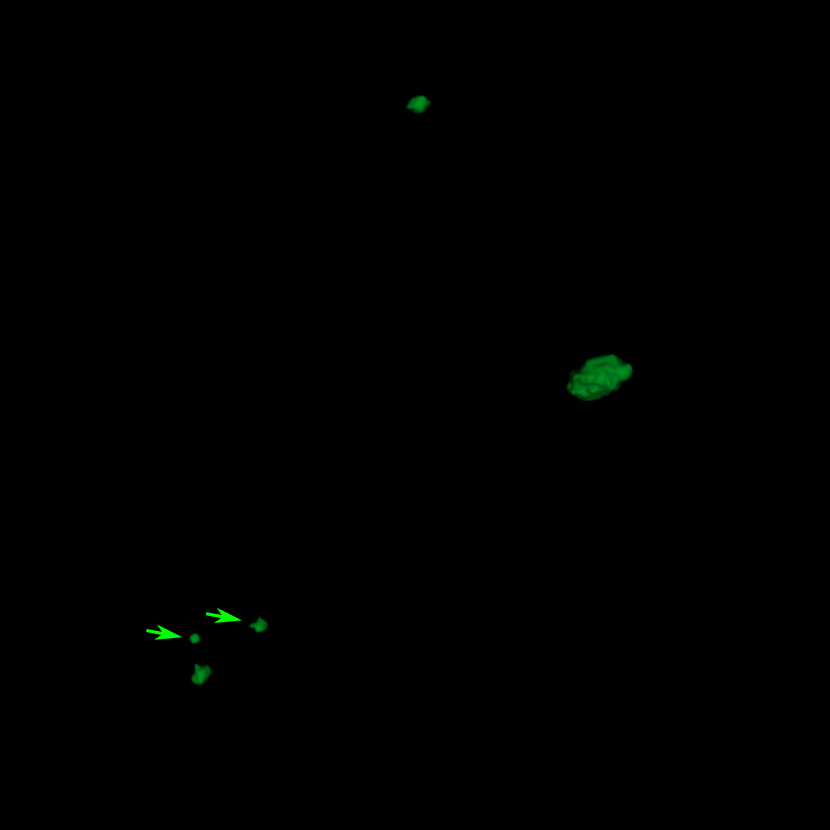

III.B. Results of DeepMedic+ using temporal prior

Fig. 5 is an example where temporal prior information is beneficial for metastasis identification. With an additional path for the prior volume, the red region in Fig. 5, as well as the other two cases in Fig. 5, is detected correctly. The sensitivity and precision for DeepMedic+ with the JVSS loss (α=0.995𝛼0.995\alpha=0.995 and α=0.5𝛼0.5\alpha=0.5) together with the temporal prior, i.e. senssubscriptsens\mathcal{M}_{\text{sens}} and specsubscriptspec\mathcal{M}_{\text{spec}} respectively, are displayed in Tab. 1. For α=0.995𝛼0.995\alpha=0.995 (senssubscriptsens\mathcal{M}_{\text{sens}}), the total number of FP metastases is reduced from 247 to 158, where 36.0%percent36.036.0\% ((247 - 158)/247) FP metastases are reduced. The average FP rate per patient is reduced from 2.40 (247/103) to 1.53 (158/103). As a trade-off, the sensitivity has a slight decrease from 0.946 (263/278) to 0.932 (259/278), with only 4 more FN metastases. Note that some of the test volumes are first scans without temporal prior volumes. If we exclude such volumes, the number of FP metastases decreases from 180 to 100 with the help of temporal prior, which is about 44.4% (180 - 100)/180 less, where 3 instead of 4 more FN metastases are observed. The average FP rate per patient is reduced from 2.54 (180/71) to 1.41 (100/71) for those with prior scans. For α=0.5𝛼0.5\alpha=0.5 (specsubscriptspec\mathcal{M}_{\text{spec}}), the sensitivity is slight worse than that of baselinesubscriptbaseline\mathcal{M}_{\text{baseline}}. However, the precision is as high as 0.996 (234/(234 + 1)) with only one FP metastasis. The FP case is displayed in Fig. 7, where the current main image together with its temporal prior and posterior images are displayed. The difference image between the main image and the temporal prior image is displayed in Fig. 7(c), where the area indicated by the arrow has larger difference. That is why specsubscriptspec\mathcal{M}_{\text{spec}} regards this region as a metastasis. However, after checking its posterior image (Fig. 7(d)), no grown metastasis exists. Therefore, we regard the detection in Fig. 7(b) as FP. But we cannot eliminate the possibility that a real metastasis has regressed at the segmented region before the posterior scan.